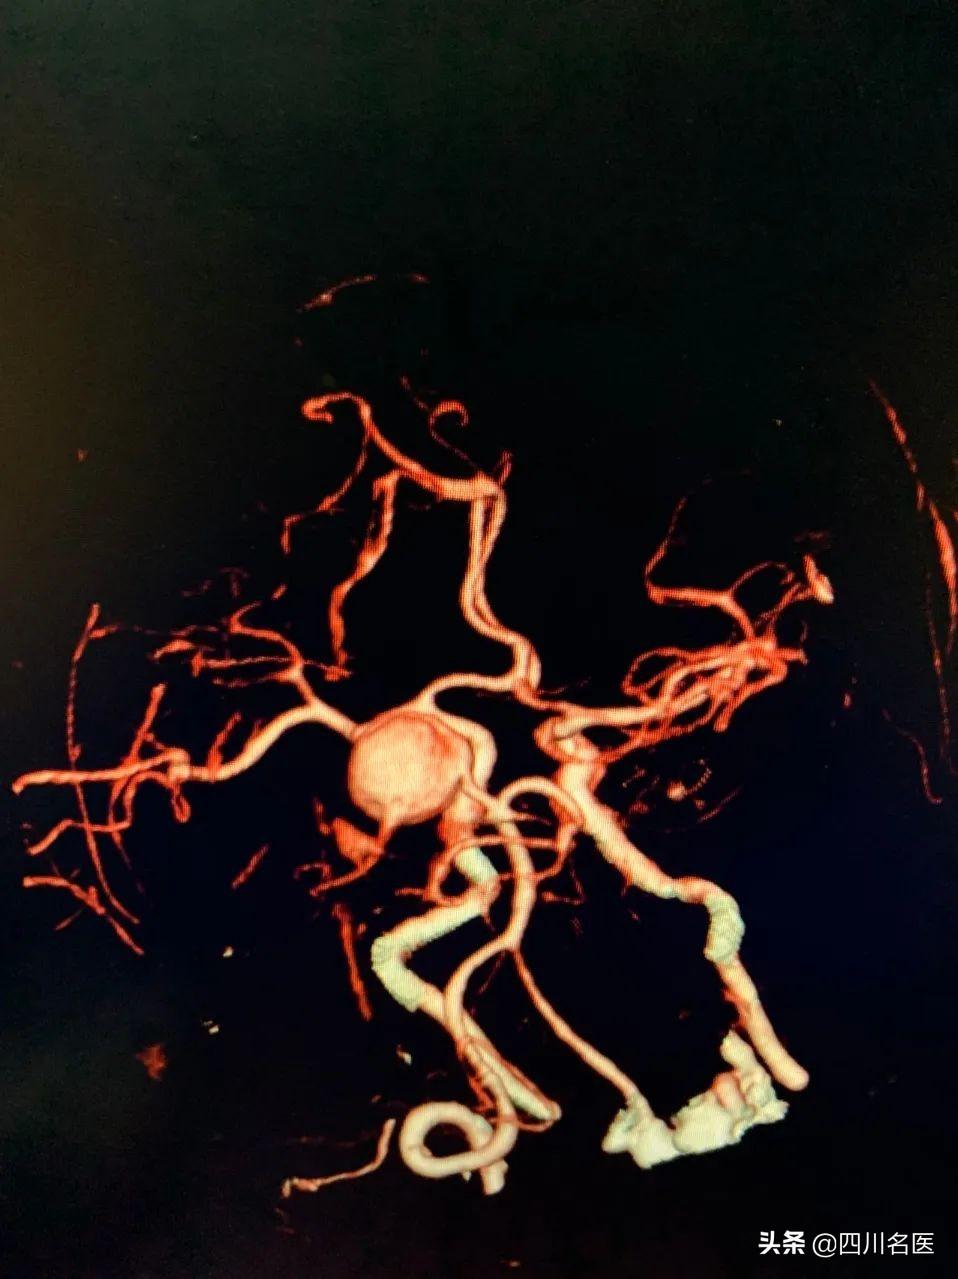

后来,李大爷被及时送到了医院,经过CT脑血管三维重建扫描(CTA)检查之后,果然发现了2个“后交通动脉瘤”。

针对本身有高血压、糖尿病或者有血管病家族史的高危人群,早期筛查可以选择:CT脑血管三维重建扫描(CTA),或者是全脑血管造影(DSA)。

目前全脑血管造影(DSA)是检查颅内血管瘤的金标准, 但这个是有创性检查,而且必须住院才能做。

刘仑鑫医生表示:针对一般人群,早期筛查可以选择CT脑血管三维重建扫描(CTA)或者磁共振三维血管成像(MRA)。